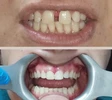

Zirkonyum uygulamalar

Porselen uygulamaları

Laminate veneer